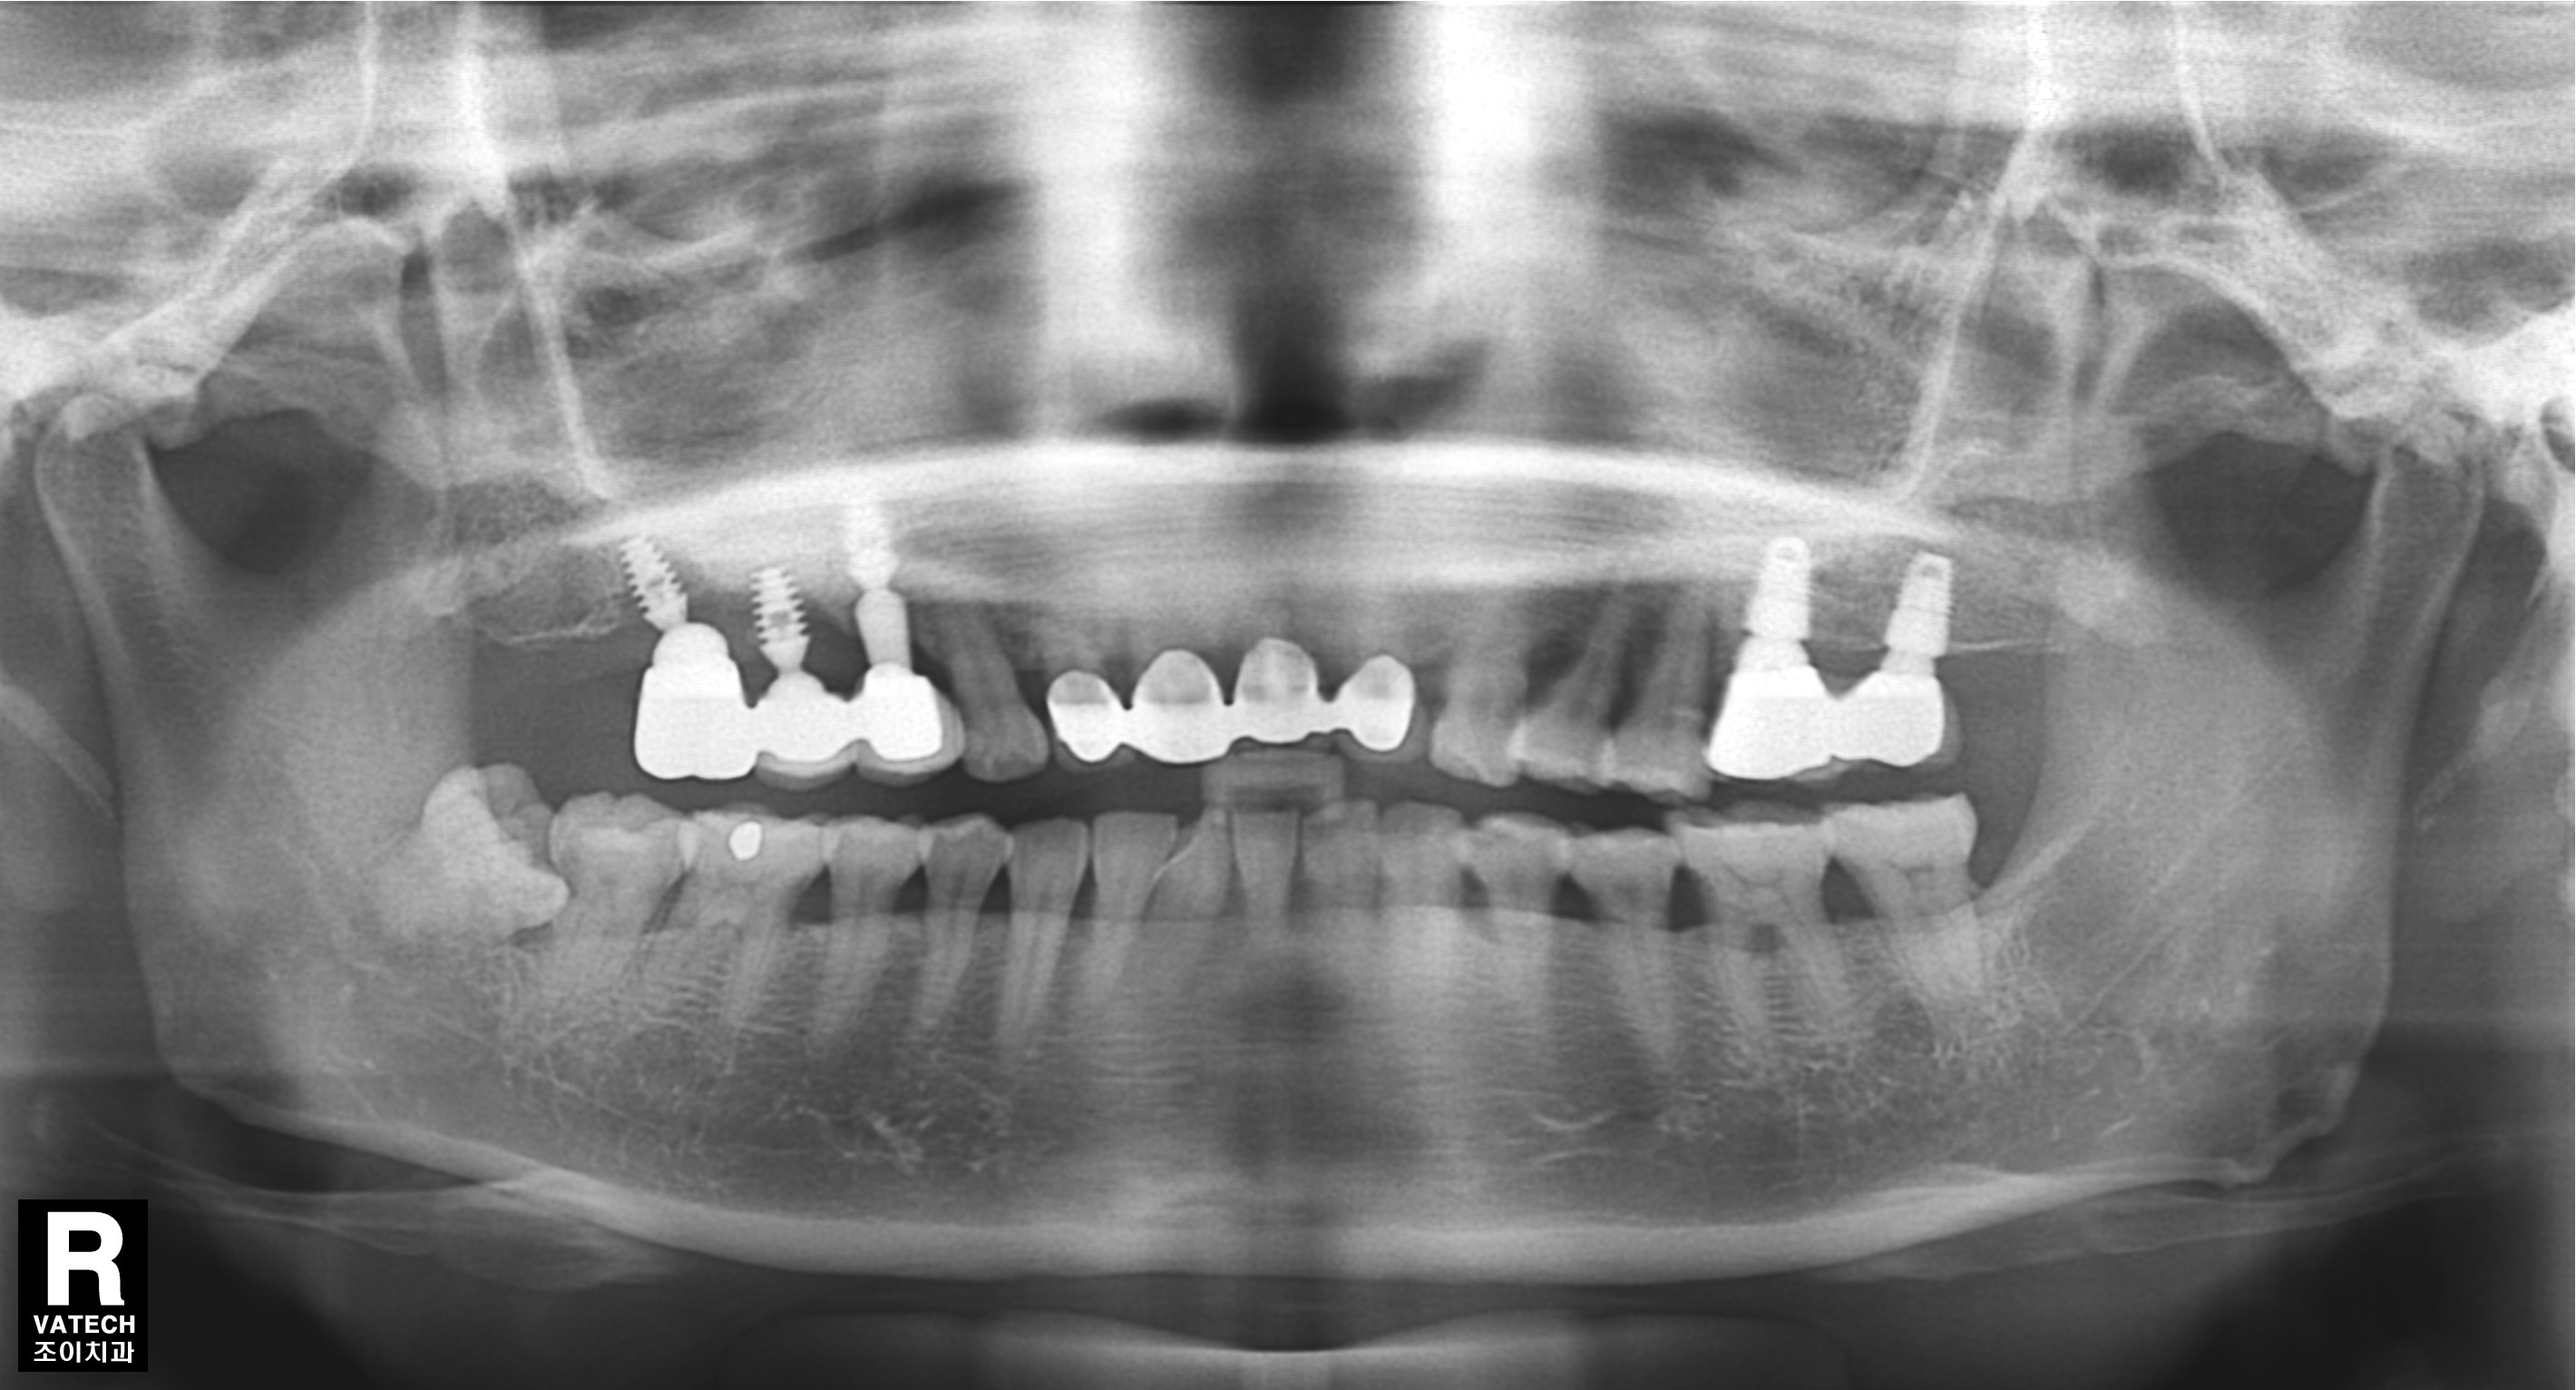

#15.16 부위로 타병원에서 수차례 실패했던 임플란트의 치료사례입니다.

임플란트 제거, 염증제거,티탄메쉬 골이식(bone graft), 서두르지 않고 충분한 경과관찰.

기본에 충실하게 step by step으로 다시 치료하는 것이 관건입니다.